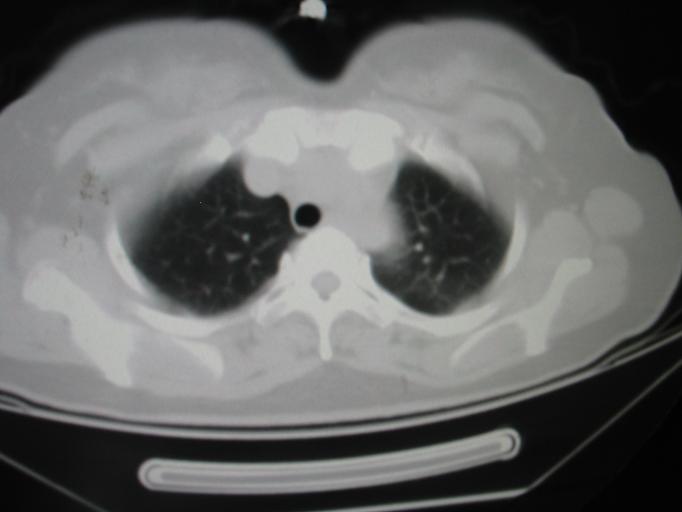

CT50266:女.40岁.咳嗽快半年.近半月来痰中带血。

女.40岁.咳嗽快半年.近半月来痰中带血。感低热.多汗。无即往史.无检查过。肺部除左上肺外无其它发现。

病变壁比囊肿、大泡厚,周围肺野呈磨玻璃样改变,考虑结核薄壁空洞

左肺下叶背段含气囊肿,肺大泡没有这样的壁。

左肺下叶背段肺囊肿。